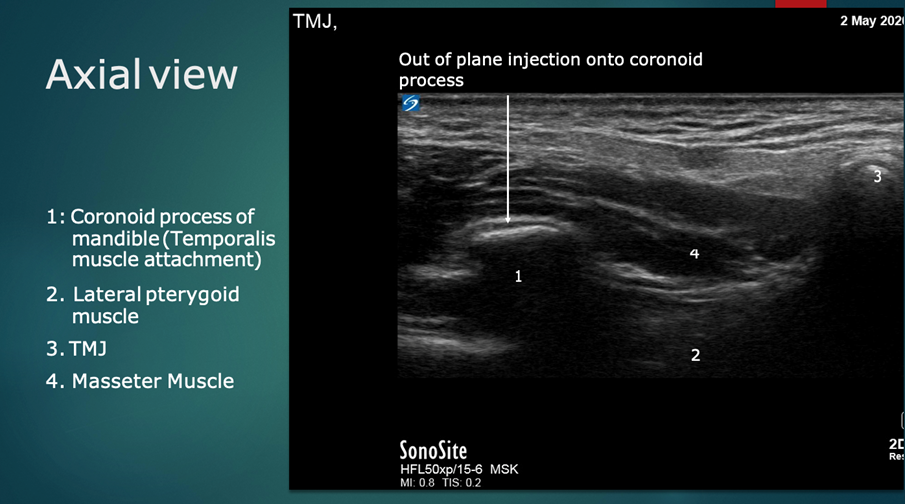

Following this, the probe is rotated 90 degrees to a transverse orientation. The mandibular coronoid process enthesis is then injected out of plane with 0.5 ml injectant. (Figures 6 and 7).

Figure 7: Ultrasound anatomy: Transverse/axial plane